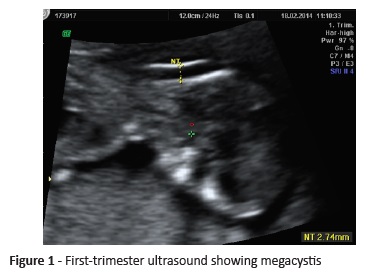

A pregnant woman with no relevant family or personal medical history was referred to our Hospital for first-trimester combined screening. US revealed a single fetus with 12 weeks and six days. Increased nuchal translucency (NT >95 percentile), megacystis, and SUA were detected. Chorionic villus sampling (CVS) was performed, with normal male karyotype result (46, XY).

Fetal death was diagnosed in the 16-week ultrasound (Figure 1). Nuchal edema and megacystis were constant features. The patient was admitted for second-trimester uterine evacuation medical protocol.